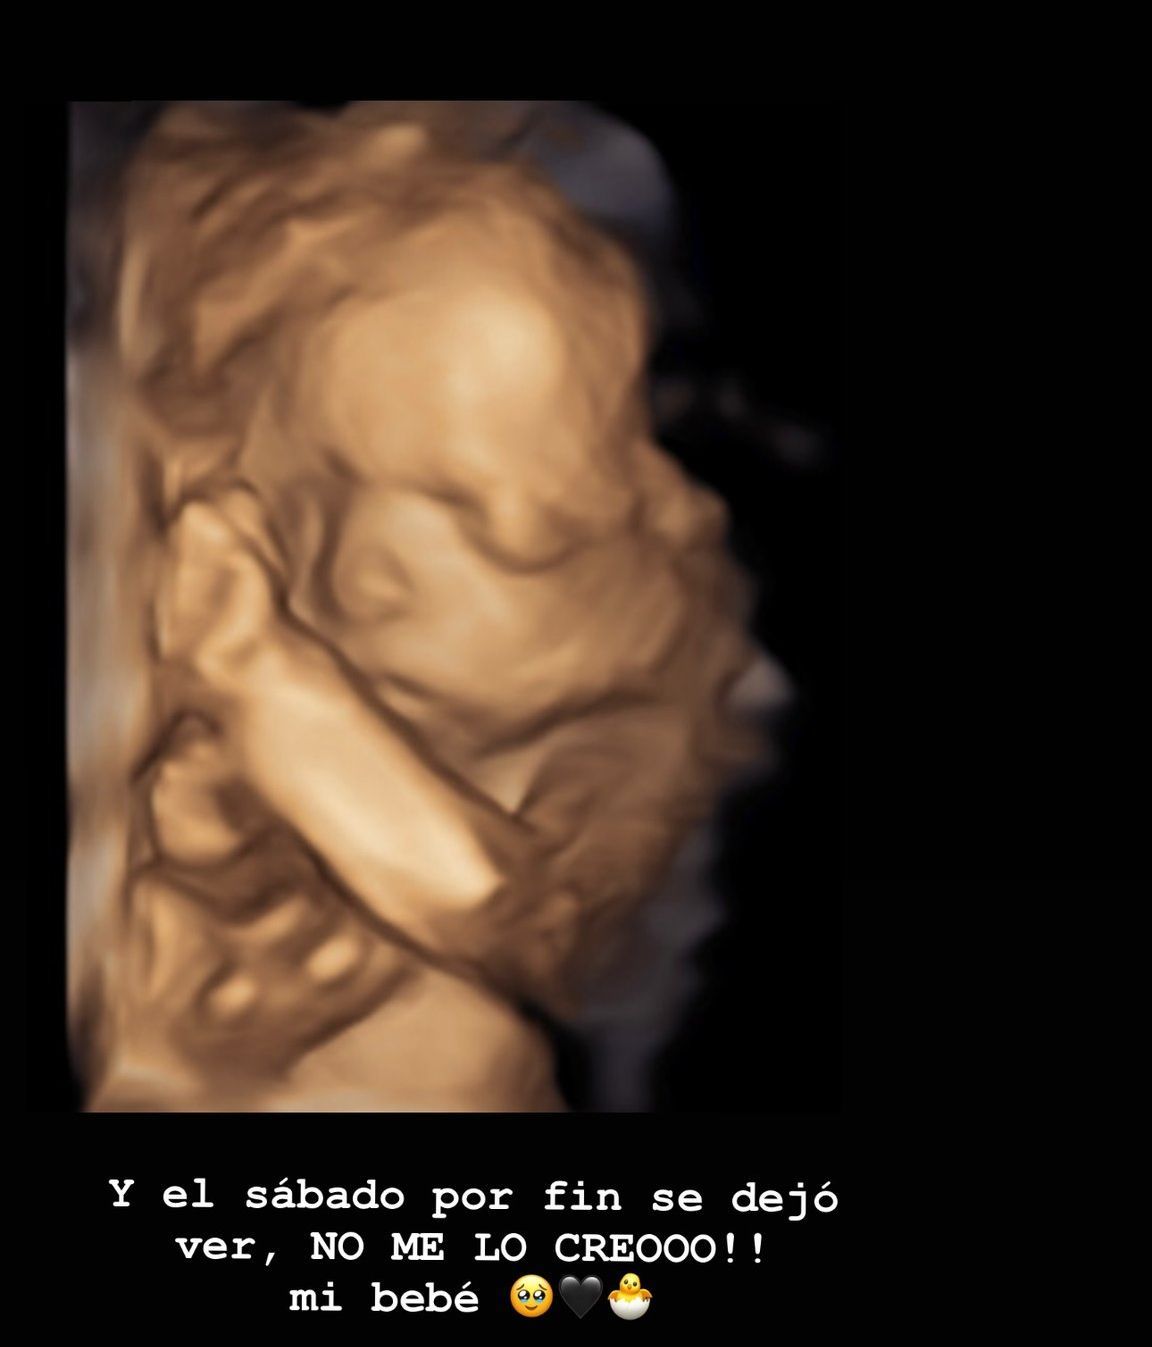

En el sonograma se puede ver a la pequeña Julieta a la perfección. Sus manitas, su rostro... estas imágenes han emocionado mucho a la creadora de contenido, que tras salir de la consulta, señalaba que su hija pesa ya "365 gramos".

"Está el corazón bien, todas las partes están perfectas así que super contenta", decía este fin de semana a través de sus redes sociales. Durante varios días, Riumbau no ha querido compartir imágenes de su hija. Sin embargo, su felicidad es tal y es tanto el cariño que está recibiendo, que finalmente se ha animado a enseñar la cara de su hija Julieta.

"El sábado por fin se dejó ver", celebra la futura mamá, para quien la siguiente imagen sea (hasta el momento en el que tenga en sus brazos a su bebé) probablemente la más importante y especial de toda su vida. "¡No me lo creo! Mi bebé", añade con una tremenda ilusión.